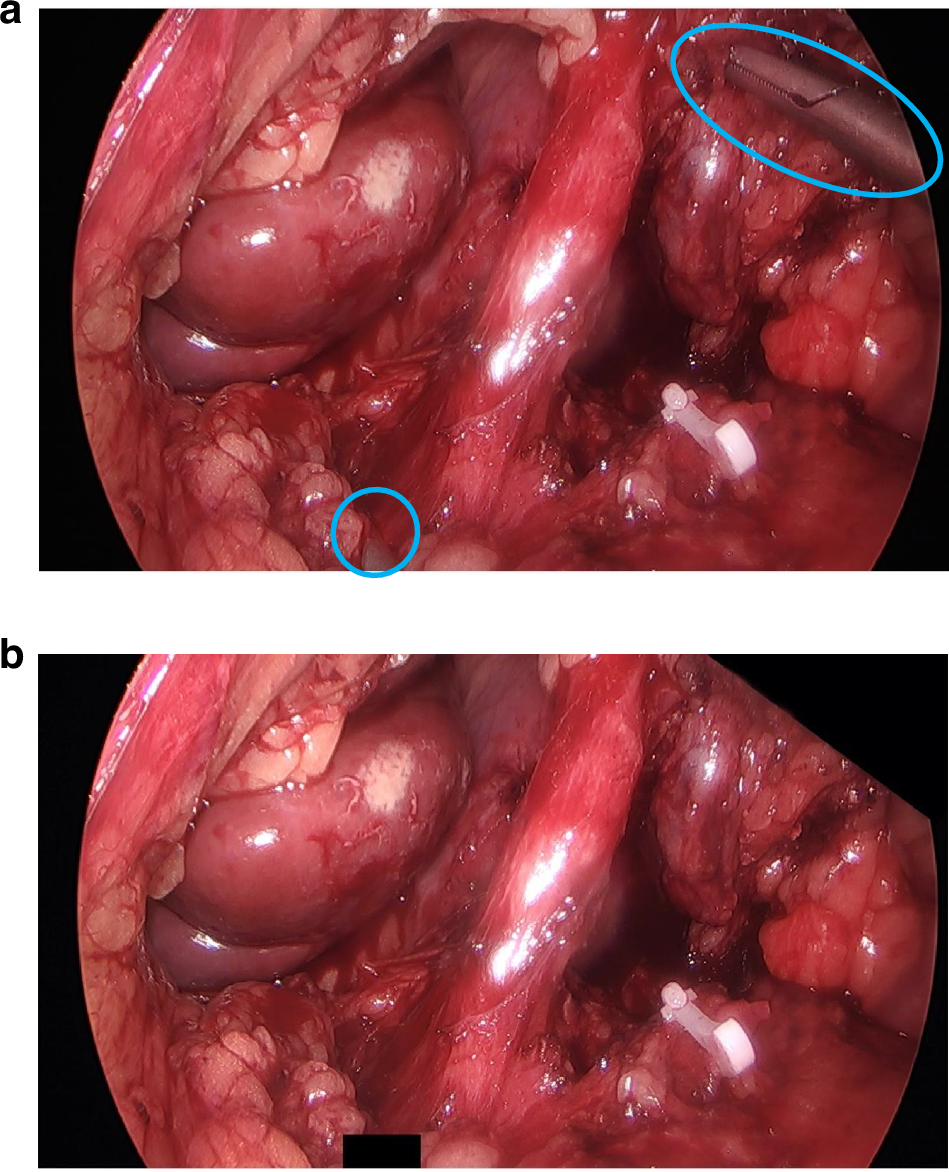

Fig. 2: Image anonymisation using ‘black boxes’.

Image a shows the identifiable objects requiring anonymisation, and image b shows the black boxes to achieve this.